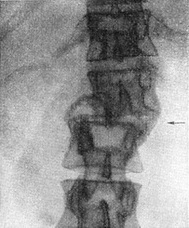

За останній час в діагностиці захворювань хребта отримали велике поширення ще дві методики рентгенологічного дослідження - пошарове (див. Томографія) і функціональний. При томографії значно збільшується роздільна здатність методу у виявленні вогнищевих та дифузних остеокластических процесів в губчатій речовині тіл хребців при таких ураженнях, як туберкульозний спондиліт, метастази злоякісних пухлин, мієломна хвороба (рис. 29). Функціональне дослідження (рентгенографія в положенні згинання П. і максимального розгинання) виявилося дуже корисним для уточнення ступеня зміщення хребців і функціонального стану міжхребцевих дисків при дегенеративних процесах в них («розхитаність дисків» при дегенеративних остеохондрозах хребта) (рис. 30, 31). Висока якість рентгенограм хребта може бути досягнуто тільки при застосуванні отсеивающих решіток, оптимальних для кожного з відділів хребта укладок і (спеціально для попереково-крижовій області) належної компресії живота люфою і компресійним поясом для рентгенографія в прямій проекції.

![]() Рис. 29. Остеокластическая форма метастазів раку молочної залози, різке розрідження губчастої речовини, патологічна компресія VII хребця. Томограма грудного відділу хребта в бічній проекції. |

При пухлинних ураженнях хребта найбільше значення має виявлення метастазів.

У той час як виявлення остеосклеротических метастазів не представляє труднощів, метастази остеокластического типу, особливо так звані дифузні, нерідко виявляються з працею. В цьому відношенні томографія надає неоціненну допомогу. Самими загальними рентгенологічними ознаками

остеоклазии при метастазах злоякісних пухлин є наступні: 1) осередкове або дифузне розрідження структури; 2) сплощення тіл хребців, часто з патологічної компресією (при цьому, на відміну від травматичної компресії, вдавлюються та каудальна, і краніальна пластинки); 3) часте поширення процесу на дужки та їх елементи; 4) відсутність звуження міжхребцевих щілин, за винятком випадків патологічних компресій з впровадженням диска в тіло хребця. Аналогічні рентгенологічні ознаки можуть давати деякі системні ураження П. і всього скелета, зокрема ендокринно-дистрофічні платиспондилии у літніх людей (так звана стареча платіспонділія), хвороба Кушинга, мієломна хвороба, ретикулезы і т. д. В багатьох випадках тільки при обліку клініко-лабораторних даних (включаючи пункцію кісткового мозку), ендокринологічного профілю і т. п. вдається розшифрувати отримані рентгенологічні дані.